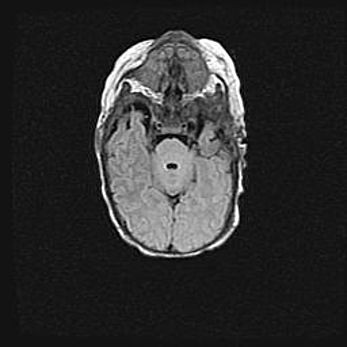

Мальформация Денди-Уокера. Киста задней черепной ямки.

Агенезия мозолистого тела.

Возраст: 2,5 месяца

Вес: 2420 г

Пол: женский

Окружность головы: 37 см

Срок гестации: 32 недели

Мальформация Денди—Уокера — редкий вид патологии ЦНС, представляющий собой врожденный порок развития каудального отдела ствола и червя мозжечка, ведущий к неполному раскрытию срединной (Мажанди) и латеральных (Лушка) апертур IV желудочка мозга. Для этогно синдрома характерна триада симптомов: гипотрофия червя мозжечка и/или полушарий мозжечка, кисты задней черепной ямки, гидроцефалия различной степени. В 70% случаев порок сочетается и с другими аномалиями головного мозга, в частности с агенезией мозолистого тела.